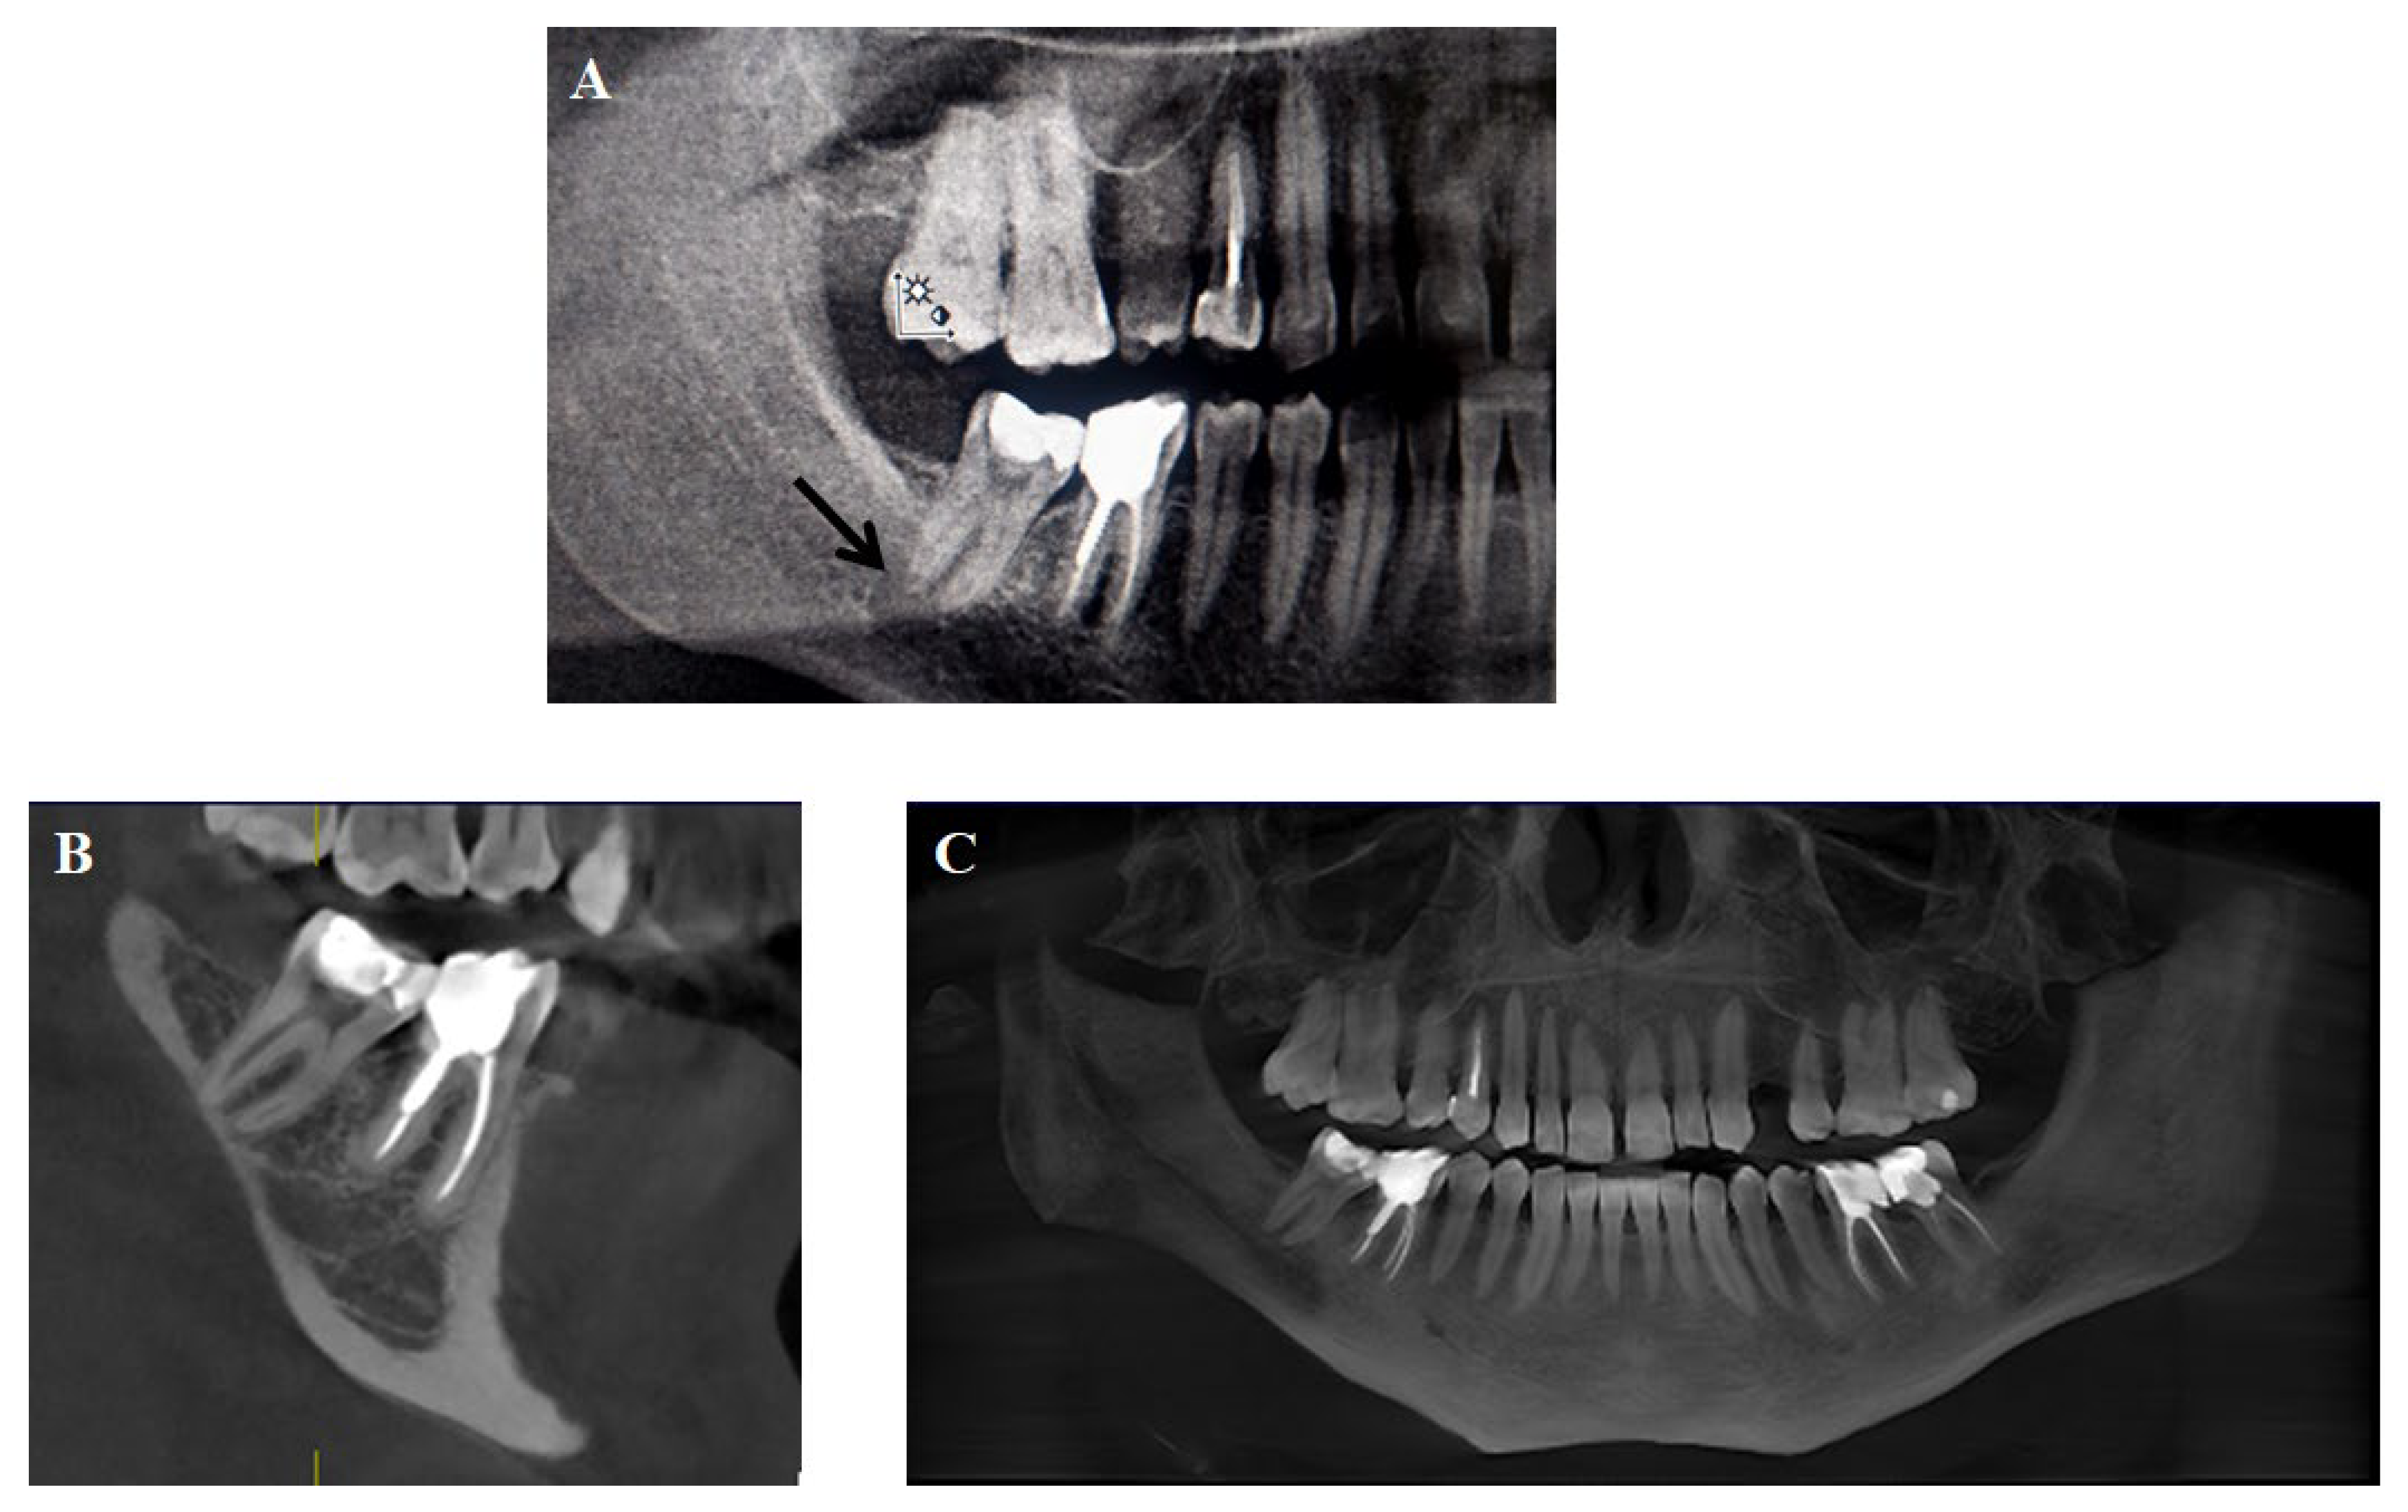

4.2. CBCT: A Foundation for 3D Visualization

5.2.1. Endodontics

- Ríos-Osorio, N.; Quijano-Guauque, S.; Briñez-Rodríguez, S.; Velasco-Flechas, G.; Muñoz-Solís, A.; Chávez, C.; Fernandez-Grisales, R. Cone-Beam Computed Tomography in Endodontics: From the Specific Technical Considerations of Acquisition Parameters and Interpretation to Advanced Clinical Applications. Restor. Dent. Endod. 2023, 49, e1. [Google Scholar] [CrossRef] [PubMed]

- Schloss, T.; Sonntag, D.; Kohli, M.R.; Setzer, F.C. A Comparison of 2- and 3-Dimensional Healing Assessment after Endodontic Surgery Using Cone-Beam Computed Tomographic Volumes or Periapical Radiographs. J. Endod. 2017, 43, 1072–1079. [Google Scholar] [CrossRef] [PubMed]